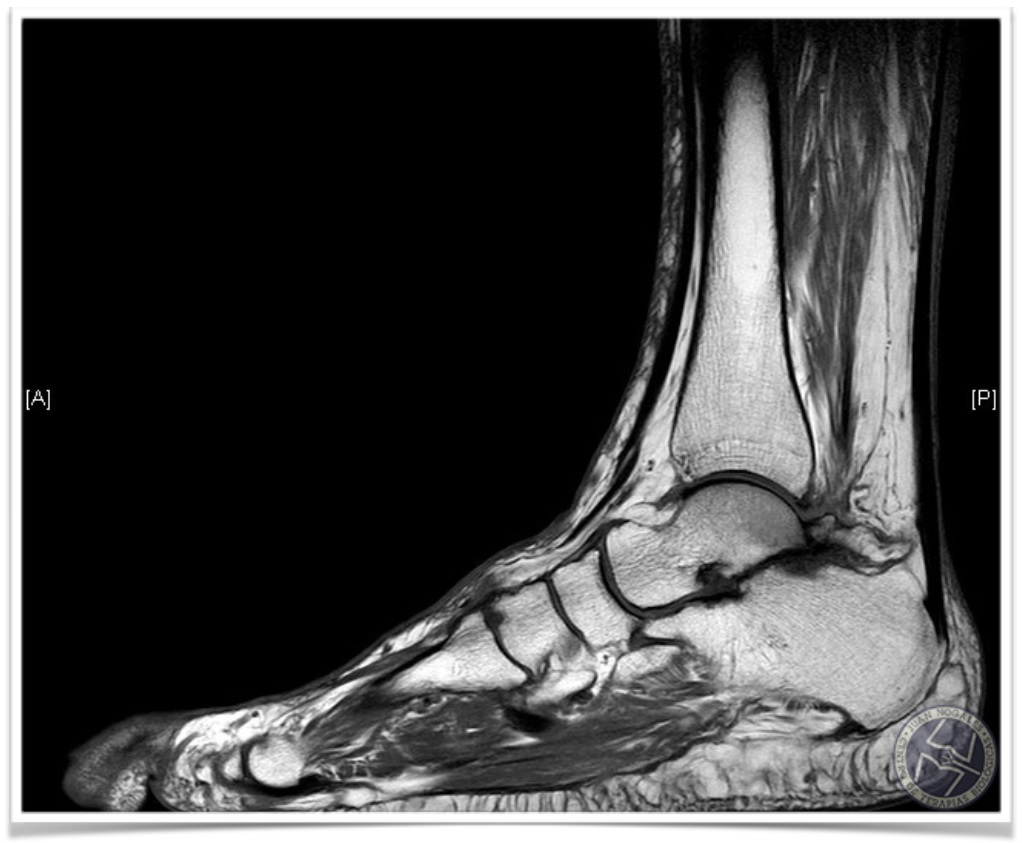

ESTUDIO POR IMAGEN: RMN

Confirmación de OS TRIGONUM en las secuencias T1 y T2

Lesion osteo-condral (LOC) en la cúpula astragalina en la zona 6.

Edema óseo en la region posterior del astrágalo.

Artrosis subastragalina